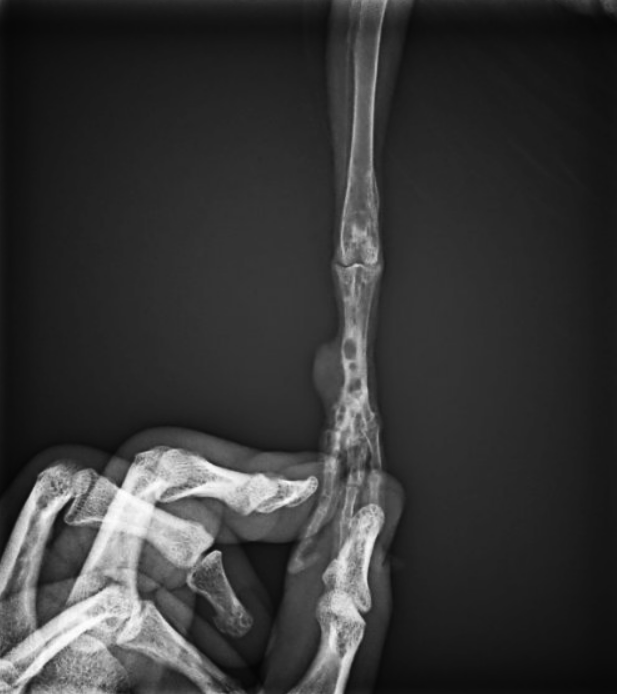

Впечатление ММБ... Но возможно ранее бывшая инфекция, от язвенного пододерматита, и пустоты- не ММБ, а старые абсцессы Броди. Связи с иными инфекциями, если таковые обнаружатся ПОСЕВОМ- почти наверняка не имеет. ТИБ предложена для исключения остеосаркомы.